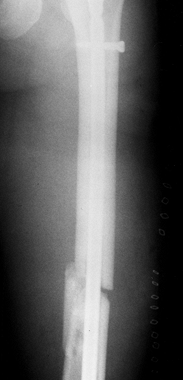

Grade II open, midshaft, slightly comminuted fracture of the left femoral shaft (Fig. 14.5). Figure 14.5. Fracture of the shaft of the left femur. Note that no fracture of the femoral neck can be seen. Figure 14.5. Fracture of the shaft of the left femur. Note that no fracture of the femoral neck can be seen.

In the lower extremity, the open midshaft femur fracture was nailed

with a nonreamed antegrade femoral nail using open technique (Fig. 14.10).

| Figure 14.10. Left femur after initial nailing. |